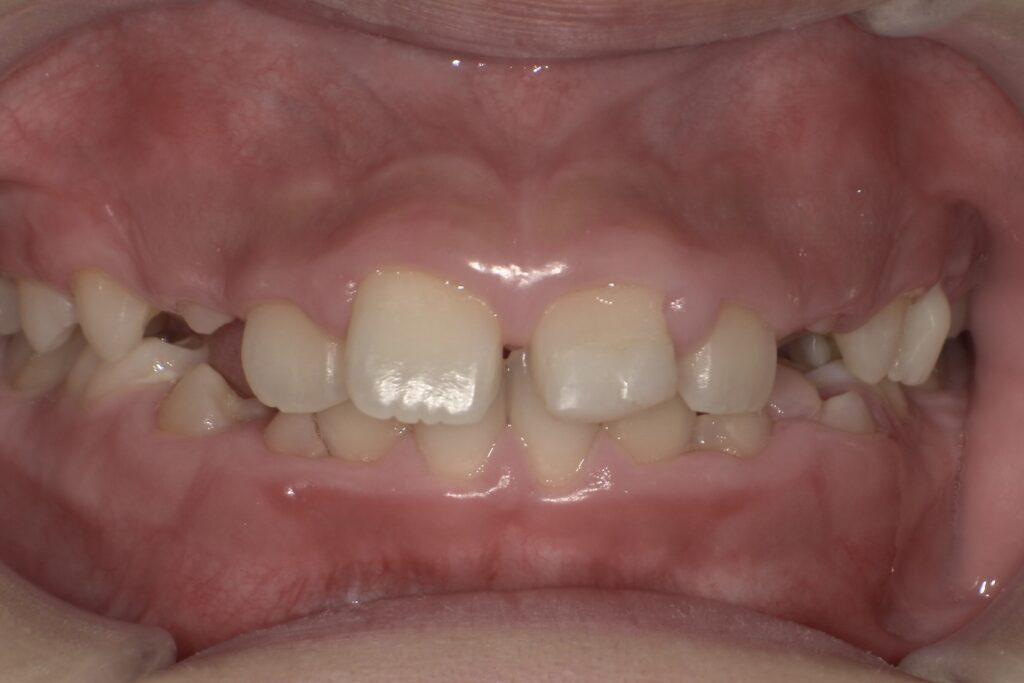

子どものすきっ歯は正常?(みにくいアヒルの子の時代)

こどものすきっ歯(正中離開)

子どもの前歯にすき間があると、心配になる保護者の方も多いですが、乳歯期に歯と歯の間にすき間があるのは正常な成長過程です。これは、将来生えてくる永久歯のためのスペースを確保する大切な役割があります。永久歯は乳歯よりも大きいため、ある程度のすき間があった方が、きれいに並びやすいとされています。

また、前歯が永久歯に生え変わる時期には、「みにくいアヒルの子の時代」と呼ばれる歯並びの変化が見られることがあります。この時期は、前歯が少し外側に開いたり、すきっ歯のように見えることがありますが、犬歯(糸切り歯)が生えてくることで歯列が押され、自然にすき間が閉じていくことが多いです。ただし、次のような場合は歯科医院での相談をおすすめします。

・永久歯が生えそろってもすき間が閉じない

・上唇小帯(上唇と歯ぐきをつなぐ筋)が強く、前歯の間に入り込んでいる

・舌で歯を押す癖(舌癖)がある

歯並びの成長には個人差があるため、気になる場合は早めに歯科医院で確認してもらうと安心です。